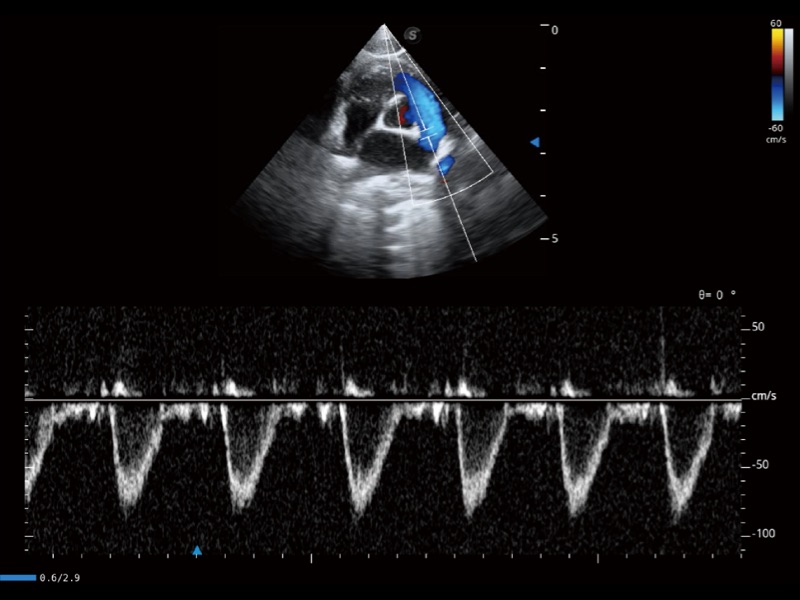

通过360度任意调节3条M型取样线,在同一心动周期上观察心脏不同位置的运动曲线,得到准确的心功能测量数据,有效评估心肌运动及左心室功能。

通过创新的 Matrix E自适应滤波器和超长时间域算法,极大提升超低速微细血流的检出能力,同时更精准地滤除软组织和噪声信号,为兽用医生提供以往无法通过常规血流获得的疾病诊断信息。